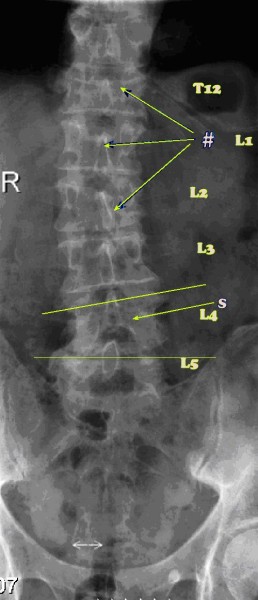

Three years later (one month ago) he consulted me. Here are the x-rays of his back.

See the fractures at T12, L1 and L2? And the severe subluxation of L4? Sorry, this is no short anecdote. Rather a long one!

Interestingly, on examination, Gys's pain was coming from none of these sites, but from L5 which was severely fixated.

X-rays are extremely useful, but sometimes they can also be very misleading. His doctor really should have x-rayed him right in the beginning, but doctors are reluctant for some reason in Holland. Gys is extremely lucky that there are no 'long tract signs' as we call them - Spinal Cord pressure causing pain, weakness and parathesias in his legs. He should have been in a brace, and confined to home for 6 weeks, in my opinion.